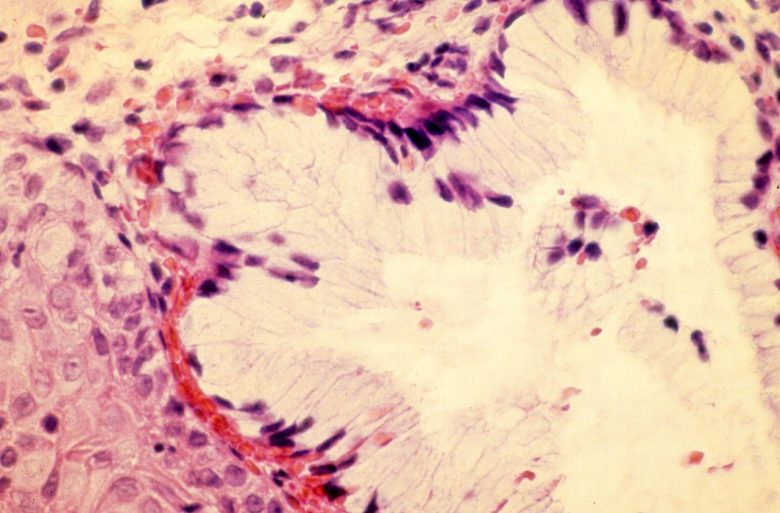

Bile duct & liver cancer

“Liver cancer includes hepatocellular carcinoma (HCC) and bile duct cancer (cholangiocarcinoma). Risk factors for HCC include chronic infection with hepatitis B or C and cirrhosis of the liver.”

Image Credit: Nephron / Wikimedia Commons.